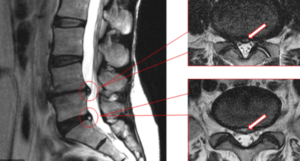

The intervertebral disc (cartilage) is located between the vertebrae. It is made up of the inner nucleus (jelly filled ) and the outer fibrous annulus ligament. It resembles an onion ring and is composed of layers. The role of the intervertebral disc is to absorb the pressure on the spine, and also has the effect of shock absorption. When we move the body, bend forward or backward, the cartilage also takes different shapes to match the body’s movements.

As people grow older and bear long-term body weight, the nucleus pulposus will begin to be dehydrated and deteriorated by the age of 35, and the ability to absorb stress will also decrease. At the same time, the fibrous annulus will begin to degenerate. When we make some improper postures or movements, it may cause some cracks (tear)in the outer fibrous ring due to compression or sudden shocks, which will cause the cartilage exert the pressure. Chemical protein leak out from the tear annular fiber and the nerve roots get irritated, that might causing pain in the lower back and feet. This condition is very common in high-intensity sports such as football and long-distance running.

Patients with fibrous ring tearing generally have several conditions: the condition is more acute, and the symptoms of getting up in the morning are more serious; Patients generally can not sit for a long time, can not stand for a long time can not move, lying down trigger pain; Patients usually have more pain in their lower backs than in their feet, and if foot pain occurs, it can extend to one or both feet; Increased pain in the lower extremities when coughing, sneezing or defecation; When examining the nerves of the lower extremities, there is referral pain (like the disc protruding), However, the scan only showed that the fiber ring tearing, and there is no disc protrusion problem, and therefore misjudged muscle or joint strain, which indirectly affecting the treatment outcome.